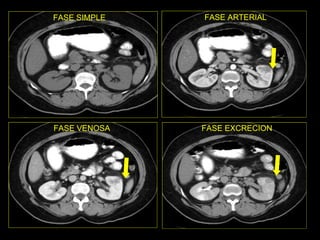

Caso # 3 ♀ , 5ta década de la vida.  Su síntoma principal fue dolor abdominal y por ello se le realizó un estudio de Urografía Excretora.  En él se sospecha de malformación arteriovenosa por lo que se envía a AngioTC. Se muestra estudio en fase simple, arterial, venosa y excretora, con cortes axiales y RMP coronales .

FASE SIMPLE FASE ARTERIAL

FASE VENOSA FASE ELIMINACION

Hallazgos Caso # 3: Estudio negativo para la sospecha clínica que motivó su realización. Y en el que se demuestra, en la fase simple sin anormalidades, y posterior  a la ministración del medio de contraste hay un área hipodensa triangular en polo superior del riñón izquierdo, la cual se mantiene durante las fases arterial y venosa del estudio.